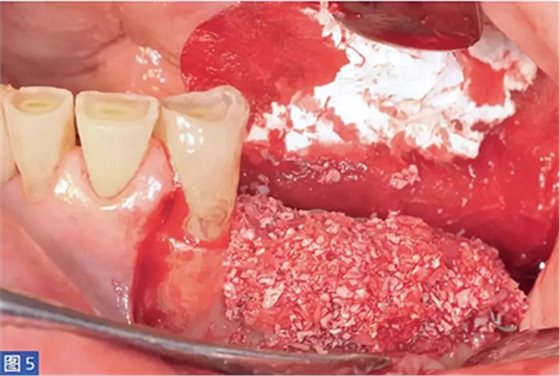

在整個(gè)手術(shù)過(guò)程中以及術(shù)后12 個(gè)月都要評(píng)估并發(fā)癥的發(fā)生。在術(shù)后12 個(gè)月,患者都要通過(guò)視覺(jué)模擬量表(VAS)對(duì)手術(shù)的滿意度從0(非常不滿意)到10(非常滿意)進(jìn)行評(píng)估。這些問(wèn)題針對(duì)對(duì)于治療過(guò)程的主觀評(píng)價(jià)。圖1-12 顯示了兩個(gè)典型病例的手術(shù)。

圖5:病例1. 在內(nèi)固定板限定空間中填塞移植物材料。